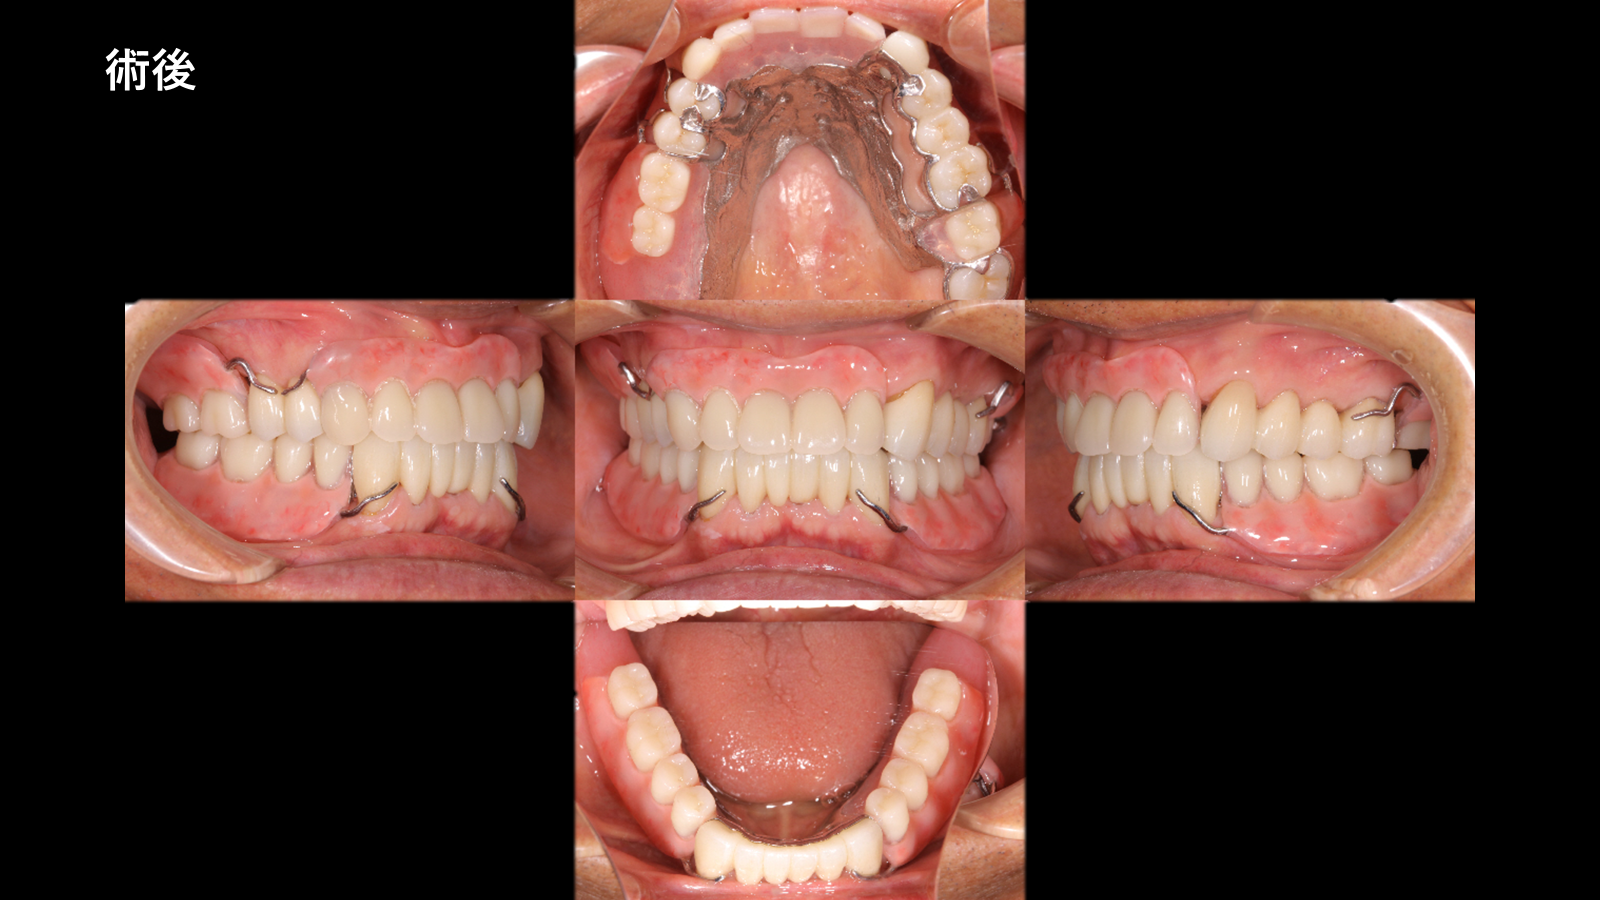

抜歯即時義歯を経て、最終的に精密設計のキャストパーシャルデンチャーへ移行した包括的再建症例です。機能回復と審美性の両立を目指した治療内容をご紹介します。

| 治療内容 | 上下ジルコニアクラウン 上下キャストパーシャルデンチャー |

| 所見 | 本症例では、咬合の不安定から歯の破折や重度の虫歯により多数歯の動揺および咬合崩壊が認められました。保存困難歯を抜歯後、即時義歯により咬合支持を確保し、治癒期間を経て最終的に自費キャストパーシャルデンチャーへ移行しました。 最終補綴では、支台歯の設計・クラスプ位置・咬合関係を精密に計画し、機能的安定と審美的改善を両立させました。 |